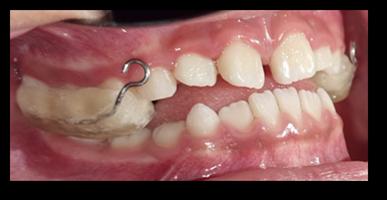

Est. Nicole Emily Rojas Espinoza1 Dr. Juan Pablo Torrico Vilte2

1 Estudiante, Carrera de Medicina, Universidad Privada del Valle. Sede Cochabamba, Bolivia. ren2015280@est.univalle.edu 2Docente, Carrera de Medicina, Universidad Privada del Valle. Sede Cochabamba, Bolivia. jtorricovilte@gmail.com

Recibido:5/1/2023 Revisado:10/5/2023 Aceptado:10/5/2023

Cita: Est. Nicole Emily Rojas Espinoza, Dr. Juan Pablo Torrico Vilte; Cirugía más inmunoterapia local en el tratamiento del tumor de Buschke-Löwenstein. A propósito de un caso. Revista De Investigación E Información En Salud UNIVALLE 2022; 18(44): p.49-53 https://doi.org/10.52428/20756208.v18i44.448

Correspondencia: Est. Nicole Emily Rojas Espinoza, Cochabamba, Bolivia, +591 70797928 ren2015280@ est.univalle.edu

Nota: Los autores declaran no tener conflicto de intereses con respecto a esta publicación y se responsabilizan de contenido vertido.

RESUMEN

El condiloma acuminado gigante o tumor de Buschke-Löwenstein (TBL) pertenece al grupo de carcinomas verrugosos; su agente etiológico se encuentra en los virus del papiloma humano (VPH serotipos 6 y 11), caracterizándose por lesiones verrugosas gigantes de localización perineal. Presentamos el caso de un paciente masculino de 28 años diagnosticado con condiloma gigante de Buschke-Löwenstein, se realizó tratamiento quirúrgico agregando imiquimod tópico como terapéutica adyuvante con excelente evolución a largo plazo.

Palabras Clave: Condiloma acuminado gigante, Tumor de Buschke-Löwenstein, Virus del papiloma humano

ABSTRACT